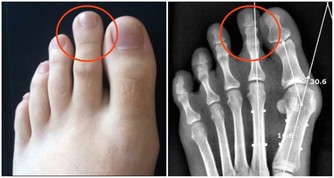

1、去醫院拍片確定關節損傷情況。